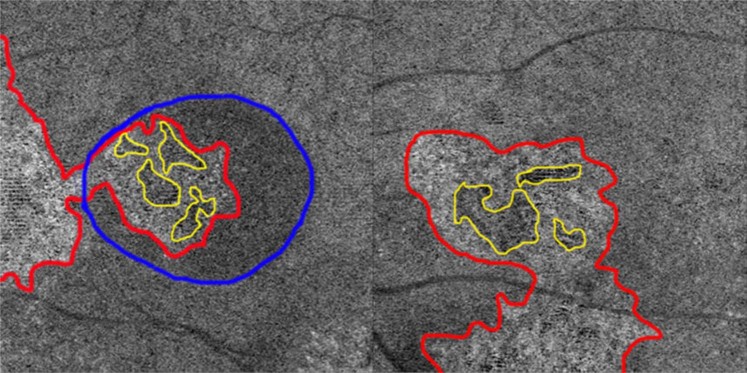

Abnormal choriocapillaris OCTA images were noticed in all 66 remained eyes. According to the abnormal patterns, three types of abnormalities were defined: type A, coarse granulated high reflective area (outlined in red in Fig. 3); type B, roundish dark halo around type A (outlined in blue in Fig. 3); and Type C, coarse granulated low reflective area (outlined in yellow in Fig. 3). Type A, B and C abnormalities were present in 61 (92.4%), 54 (81.8%), 66 (100%) eyes, respectively. There were 54 (81.8%) eyes that exhibited all three types abnormalities, 7 (10.6%) had type A and C abnormalities, and 5 (7.6%) only had type C abnormalities.

Figure 3.

Three main types of abnormalities were found in choriocapillaris optical coherence tomography angiography (OCTA). Type A (outlined in red), was defined as coarse granulated high reflective area; type B (outlined in blue) was defined as the roundish dark halo around type A; and type C (outlined in yellow) was defined as the coarse granulated low reflective spot inside type A. The left panel image shows a representative case with all the three types of abnormalities on choriocapillaris OCTA. The right panel is a representative case without type B abnormality.